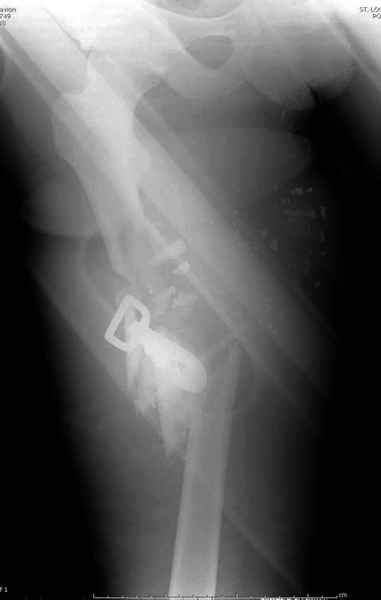

2 перелом бедра